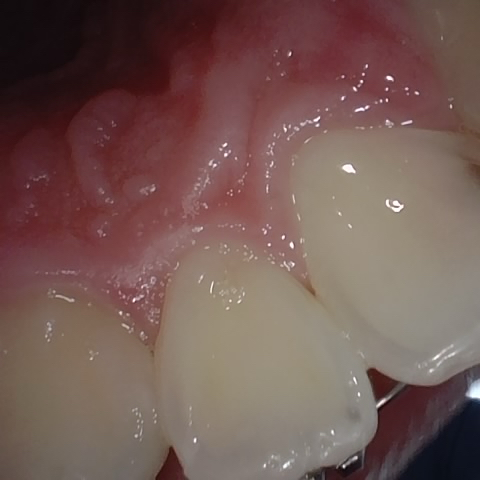

Incorrect Quality Level

The reference annotation for this image is

None

.

Please select the correct quality level.

Annotated as "Good"